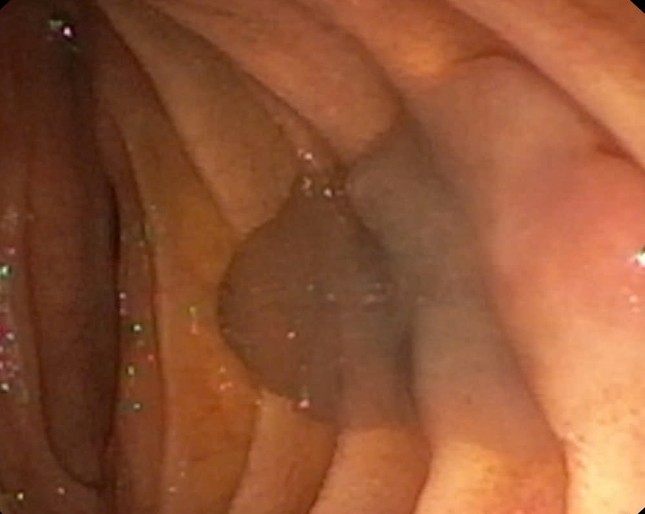

Sán lá gan được phát hiện trên hình ảnh camera nội soi

BS Nguyễn Đình Tùng cho biết: “Trong quá trình nội soi mật tụy ngược dòng, quan sát dưới màn hình C-Arm nhận thấy ống mật chủ của bệnh nhân giãn khoảng 10mm, đoạn cuối có bóng nhỏ không ngấm thuốc. Sau đó, các bác sĩ tiến hành cắt nhú vater, dùng bóng kéo ra được con sán lá gan kích thước khoảng 20mm ra khỏi cơ thể người bệnh. Mẫu sán được xét nghiệm định danh là sán lá gan lớn”.

Bằng phương pháp nội soi mật tụy ngược dòng (ERCP) các bác sĩ đã bắt được con sán lớn ra khỏi cơ thể người bệnh